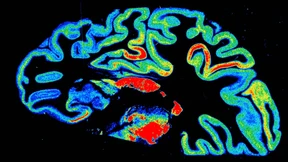

Armut beeinträchtigt das Gehirn von Kindern

Wachsen Kinder in Armut auf, beeinträchtigt das die Gehirnentwicklung messbar. Wissenschaftler stellten jetzt fest, dass eine gute Bindung zwischen Eltern und Kindern diesen Effekt abschwächen könnte.